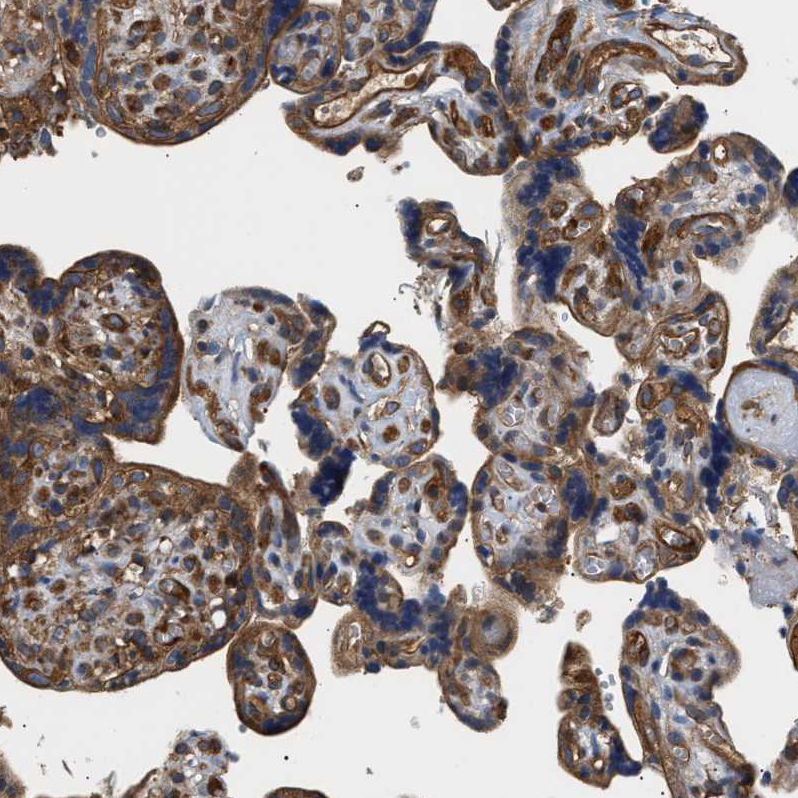

Immunohistochemical staining of human lymph node, placenta, stomach and testis using Anti-SAMD9L antibody HPA019461 (A) shows similar protein distribution across tissues to independent antibody HPA019465 (B).